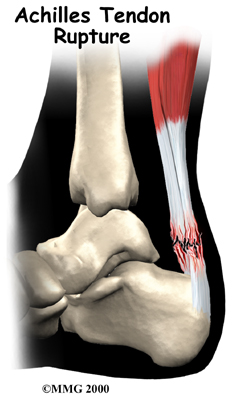

Achilles Tendon Rupture

In severe cases, the force of a violent strain may even rupture the tendon. The classic example is a middle-aged tennis player or weekend warrior who places too much stress on the tendon and experiences a tearing of the tendon. In some instances, the rupture may be preceded by a period of tendonitis, which renders the tendon weaker than normal.

An Achilles tendon rupture is usually an unmistakable event. Some bystanders may report actually hearing the snap, and the victim of a rupture usually describes a sensation similar to being violently kicked in the calf. Following rupture the calf may swell, and the injured person usually can't rise on his toes.

Nonsurgical treatment for an Achilles tendon rupture is somewhat controversial. It is clear that treatment with a cast will allow the vast majority of tendon ruptures to heal, but the incidence of rerupture is increased in those patients treated with casting for eight weeks when compared with those undergoing surgery. In addition, the strength of the healed tendon is significantly less in patients who choose cast treatment. For these reasons, many orthopedists feel that Achilles tendon ruptures in younger active patients should be surgically repaired.

Nonsurgical treatment might be considered for the aging adult who has an inactive lifestyle. This allows the patient to heal while avoiding the potential complications of surgery. The patient's foot and ankle are placed in a cast for aprroximately eight weeks. Casting the leg with the foot pointing downward brings the torn ends of the Achilles tendon together and holds them until scar tissue joins the damaged ends. During this time, your physical therapist will instruct you in safe and proper crutch utilization. After your cast is removed, our physical therapist can have your fitted with a large heel lift to wear for apprximately another six to eight weeks after the cast is taken off.

Surgery may also be suggested if you have a ruptured Achilles tendon. Reattaching the two ends of the tendon repairs the torn Achilles tendon. This procedure is usually done through an incision on the back of the ankle near the Achilles tendon. Numerous procedures have been developed to repair the tendon, but most involve sewing the two ends of the tendon together in some fashion. Some repair techniques have been developed to minimize the size of the incision.